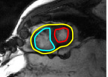

In cardiac image analysis, there are multiple structures (the right and left ventricles, and myocardium) that all useful and should be segmented. Our method is easily adaptable to this case. Indeed, computation of in Section III-C can be readily generalized. In general, multiple level sets should be used to represent multiple regions. However, in our case of interest (ventricles and surrounding epicardium), the regions form a rather simple topology (see Figure 3), and all regions can be represented using a single level set.

While theoretically for each will be an invertible/onto map in each individual region, and thus regions cannot change topology, numerically, between close by structures, merging/splitting may occur. Since we know that, in our application of interest, there is no such topology change, we enforce a hard topology constraint, that topology must not change during the level set evolution. This is now standard with level sets using discrete topology preserving techniques [14]. The original level set evolution is augmented with a step that looks for non-simple points that change sign in a level set update, i.e., locations of topology change. Such points are not allowed to change sign, and this preserves topology. Non-simple points are easily detected with local pixel-wise operations, and this makes implementation easy and the technique adds very little computational cost. The reader is referred to [14] for details on the criteria for simple points.